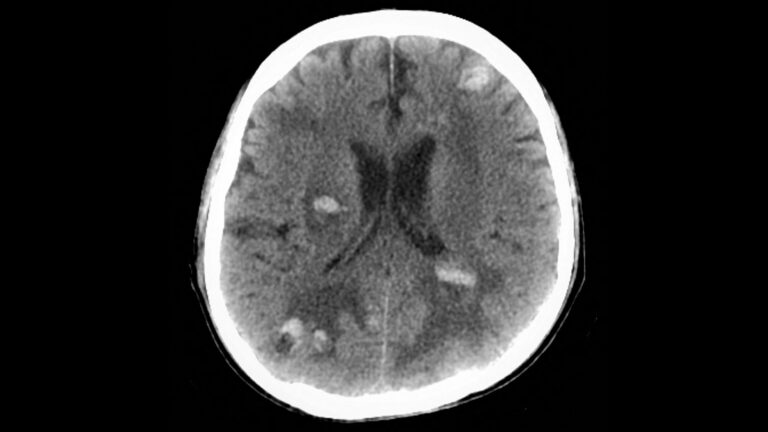

GLP-1 Drugs May Benefit Cancer Patients With Brain Lesions

(MedPage Today) -- GLP-1 receptor agonist use was associated with a lower risk of death in cancer patients with brain metastases and type 2 diabetes, a retrospective cohort study found.

Within 3 years of a first recorded brain metastasis, patients...